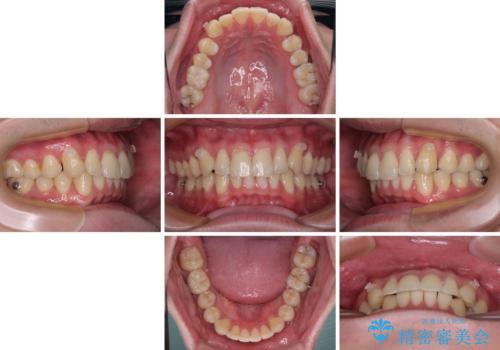

お仕事が忙しく、1日の装着時間は不十分となる日もありましたが、治療は順調に進めていくことができました。

途中、以前大きなむし歯で処置をした歯が痛み出し、根管治療が必要となったため、根管治療とオールセラミッククラウンによる補綴治療を行い、その後にインビザラインによる仕上げの歯列移動を行い、無事に治療を終えることができました。